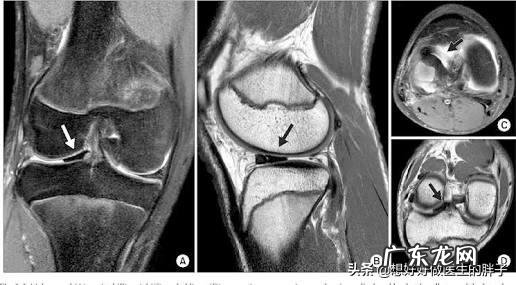

针对题主的疼痛特点以及工作性质,考虑可能是以下两种情况,我们简单的分析下:髌前脂肪垫炎症导致的疼痛髌前脂肪垫是位于膝关节髌腱后方的一团脂肪团块,可以起到分泌关节液,填充关节腔等重要的作用 。在长时间的久站久坐或者是蹲着的过程当中,就会有可能对髌前脂肪垫造成比较大的压力,产生无菌性的炎症,导致患者出现关节的疼痛,尤其是在休息有的启动阶段和上下楼梯的时候产生疼痛 。

如果从厨师的职业角度来帮助患者理解这块脂肪垫的话,他就有点儿像是鸡爪子正中的掌中宝,是一团结缔组织 。在膝关节的位置如下图所示,如果患者存在着髌前脂肪垫炎,按压这个部位会产生比较明显的疼痛 。